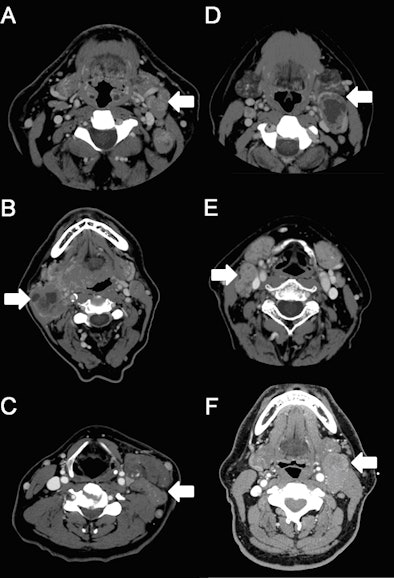

Matted lymph nodes are lymph nodes larger than 1 cm that feel connected and seem to move as a unit. On a CT image, a matted lymph node appears to overlap with another lymph node, whereas a "regular" lymph node does not.

| CT scans demonstrating examples of matted nodes (A-C) and nonmatted nodes (D-F). The nodes are noted with arrows. Image courtesy of University of Michigan Comprehensive Cancer Center. |